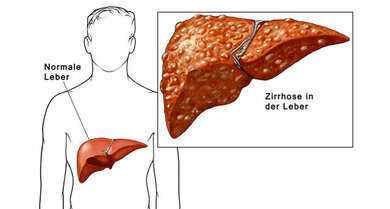

Meist entsteht Leberkrebs auf dem Boden einer vorgeschädigten, zirrhotischen Leber

© Mauritius/Alamy/Nucleus Medical Media Inc.

Hauptursache für die Entstehung von Leberkrebs weltweit ist eine vorerkrankte Leber, in 90 Prozent der Fälle entstehen sie auf dem Boden einer Leberzirrhose (bindegewebiger Umbau der Leber). Die Ursachen für eine Zirrhose sind vor allem starker Alkoholkonsum, chronischen Hepatitis-Infektion (Hepatitis-B, Hepatitis-C) oder einer nicht-alkoholisch bedingte Fettlebererkrankung. Letztere spielt eine zunehmende Rolle und wird durch Übergewicht und Fettleibigkeit (Adipositas), einer Zuckerkrankheit (Diabetes mellitus) oder einem metabolischen Syndrom (eine Kombination aus erhöhten Blutfett- und Blutzuckerwerten sowie erhöhtem Blutdruck, meist findet sich auch eine stammbetonte Fettansammlung) ausgelöst. Seltener sind angeborene Stoffwechselerkrankungen wie die Eisenspeicherkrankheit (Hämochromatose) oder Kupferspeicherkrankheit (Morbus Wilson) für die Entstehung einer Leberzirrhose verantwortlich. Giftige Substanzen wie Tetrachlormethan (findet sich in der Metallverarbeitung) oder sehr selten auch Medikamente wie Methotrexat können ebenfalls eine Leberzirrhose auslösen und begünstigen damit die Entstehung von Leberkrebs.